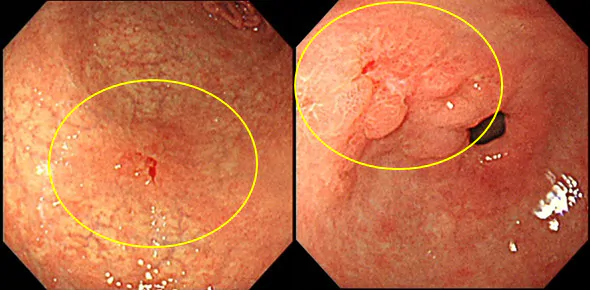

丸で囲まれた部分が早期胃がんです。ここまでなら内視鏡で治療可能です。

丸で囲まれた部分が進行胃がんです。これは手術しかありません。